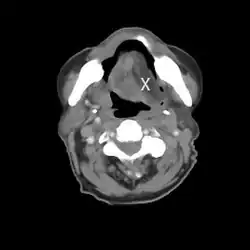

Einseitige Zungenatrophie bei Hypoglossusparese links (rechts normal [X]; CT-Bild)

Einseitige Schädigungen des Nerven führen zu einer halbseitigen Lähmung der Zunge (Hemiglossoplegie) mit Abweichung zur erkrankten Seite. Es können Schwierigkeiten bei der Nahrungs- und Flüssigkeitsaufnahme und Artikulationsstörungen auftreten. Beidseitige Schädigungen führen zu einer vollständigen Zungenlähmung (Glossoplegie), eine längere Schädigung zu einer Atrophie der Zungenmuskulatur.